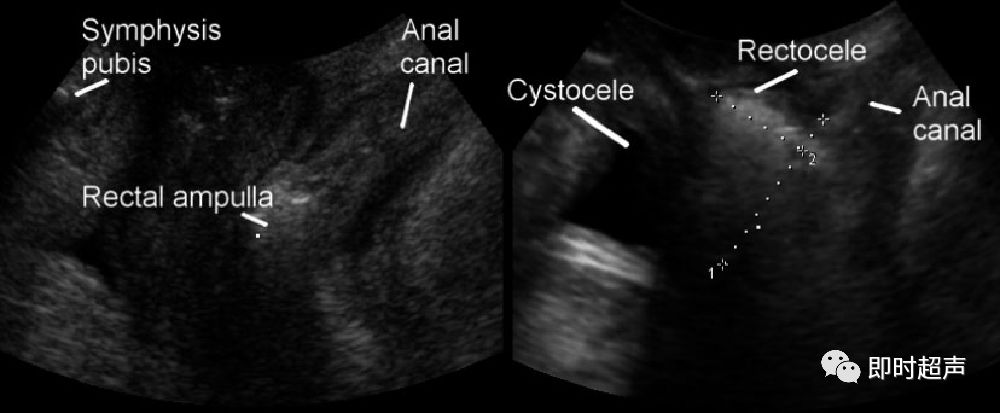

膀胱膨出

后腔室脱垂

后盆腔功能障碍主要指直肠膨出和会阴体组织的缺陷,表现为直肠功能障碍的疾病

后腔室脱垂包括会阴运动过度、肠疝和直肠真性膨出。

直肠膨出

直肠膨出:又称为阴道后壁膨出,亦称为直肠阴道膨出或者直肠阴道疝。该膨出物与肛管约呈90度夹角。

肛门直肠肌明显不连续,疝出深度约1.9cm,长度约3.3cm。

会阴过度运动

会阴体组织缺陷导致的会阴体下降,超声表现为直肠壶腹部位于耻骨联合后下缘水平线下方,与该参考线的垂直距离≥15mm,肛门内括约肌回声连续。膨出物与肛管间夹角呈钝角。